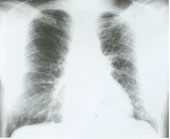

非特異性間質肺炎1.胸部X線檢查:常見徵象是兩肺瀰漫性間質滲出,呈網狀或磨玻璃樣,也可以是正常胸片。

1.常規胸片 以中下肺野及胸膜下為主 雙側肺有較均勻分布的間質浸潤陰影,可呈磨玻璃樣 隨著病情發展出現線條狀及網狀或結節狀陰影,但很少出現蜂窩肺 偶出現亦為極少量。晚期肺體積可縮小。

(1)磨玻璃陰影:為片狀模糊浸潤性陰影,內可見血

管紋理 主要分布在中下肺野與胸膜下,約80%病人出現此種陰影,但很少為惟一的陰影,多對稱。